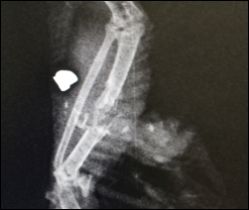

Schockierendes Röntgen

Dabei stellte sich heraus, dass es sich um eine beringte Brieftaube, also ein Haustier, handelte. Der Vogel hatte eine schwere Verletzung am rechten Flügel, die stark nach einer Schussverletzung aussah. Ein Röntgen bestätigte den Verdacht und zeigte das Ausmaß der Verletzung.

Im Flügel der Taube steckte ein Projektil, durch dessen Einschlag Elle und Speiche derart zerfetzt wurden, dass der Tierärztin keine andere Wahl blieb, als das Tier zu erlösen.